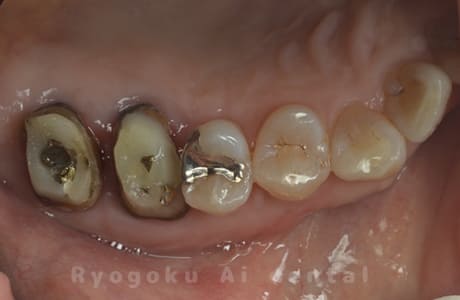

Case09

-

- 原因

- 左上6番重度カリエス

- 治療内容

- クラウンレングスニング

- 治療費用

- 44,000円(根管治療、補綴は別途費用)

他院で抜歯と判断された歯です。クラウンレングスニングを行い、保存を試みました。現在も問題なく被せ物が入り、使用できてます。

<リスク・副作用>

手術後は痛み、腫れ、痺れ、青あざなどの副作用が生じます。痛みは痛み止めを処方しますが、腫れ、青あざは1週間程度生じる場合があります。また、部位によっては神経の走行が複雑で、痺れが残り、長期的にお薬を処方する場合があります。